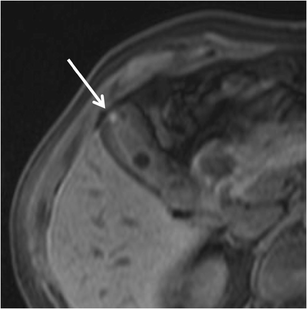

The use of high-frequency probes (Fig. 6) increases US accuracy in the diagnosis of GA. Indeed, GA often involves gallbladder fundus, which is usually unsatisfactorily evaluated by means of the classical 4–5-MHz convex probes; every suspicious finding in this area must be further investigated by means of higher frequency (7–9 MHz) linear probes for better characterization.

Fig. 6

US of gallbladder adenomyomatosis: use of different frequencies probes. In this patient with diffuse GA, the gallbladder wall is poorly evaluable by means of a conventional 5-MHz convex probe (a). Using a high-resolution 7-MHz linear probe (b) hyperechoic Rokitansky–Aschoff sinuses (arrows) can be highlighted within a diffusely thickened gallbladder wall; moreover, the serosa maintains sharp margins (arrowheads)

Bild vergrößern